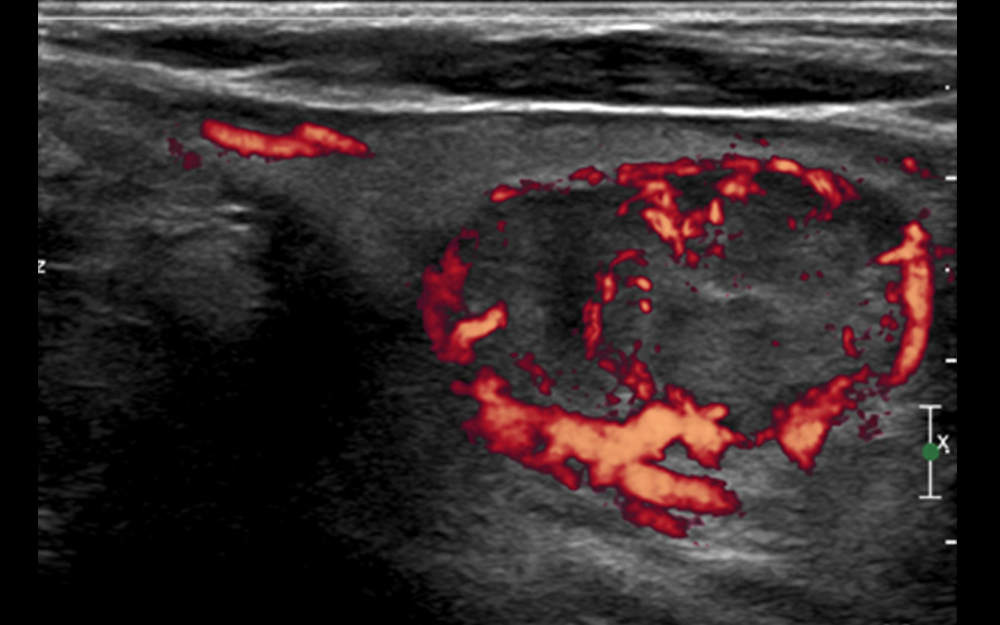

The mission of the Endocrinology, Diabetes and Metabolism Fellowship Program at Ochsner Medical Center is to educate fellows in a primarily clinical setting solidly grounded by large clinical and procedural volumes and faculty strongly engaged in clinical and didactic teaching. We incorporate a diverse training ground which boasts a tertiary care center, sub specialized clinics and advanced training in the fields of neck ultrasonography, fine needle aspiration and DXA readings.